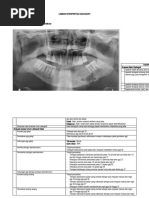

ANATOMI RADIOGRAFIK

Gambaran-gambaran Anatomi (normal) yang tampak dalam

Radiografik Gigi, Jaringan Penyangga dan Rahang

FASE GELIGI PERGANTIAN

FORAMEN INSISIVUS

FORAMEN MENTALE